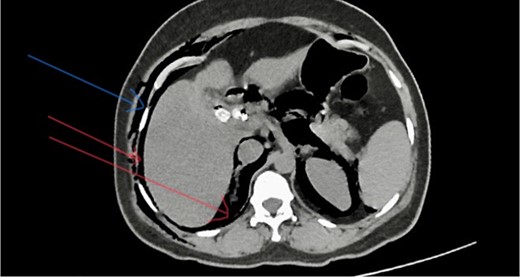

She has undergone a semi-elective ERCP in a semi-prone position, under sedation with propofol target-controlled infusion. Major papillae identified with side viewing endoscopy. Guidewire was inserted into CBD, and a cholangiogram was done. It showed dilated CBD up to 1.3 cm, mild dilated hepatic ducts, and a large radiolucent area in the distal CBD (around 1.5 cm). Sphincterotomy was done with a sphincterotome, and the ampulla was dilated up to 1.5 cm with a balloon dilator. Then, a balloon retrieval was attempted and failed, probably due to a stone sticking to the CBD wall. Then, a mechanical lithotripter was used to break the stone, but it failed, damaging the instrument. During the procedure, her oxygen saturation dropped to 75–80%, and she developed surgical emphysema in the face, neck, and upper chest region. In addition, she developed abdominal distention as well. Immediately, she underwent CBD stenting with a 12-cm, 10 French Gauge double pigtail biliary stent and changed her position to supine. Then, she was intubated with rapid sequence induction, and a nasogastric tube was inserted and transferred to the surgical intensive care unit. Post-ERCP, non-contrast computed tomography (NCCT) of the abdomen and chest showed extensive pneumo-peritoneum and retroperitoneal gas with subcutaneous emphysema (Figs 2 and 3). There was no evidence of air leakage on NCCT and no clinical features of peritonitis on subsequent days. So she was managed non-surgically with nasogastric tube (NG), nil by mouth, intravenous fluids with intravenous antibiotics. Clear fluid was started after 24 hours slowly via NG.

Post-ERCP NCCT abdomen shows pneumo-peritoneum (red arrow), pneumo-retroperitoneum, and subcutaneous emphysema (blue arrow)

Post-ERCP NCCT abdomen shows pneumo-retroperitoneum (red arrow).